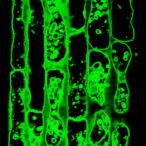

“When insulin binds to its receptor on the endothelium and activates it, this leads to an expansion of the blood vessel diameter and improved permeability of the vessel wall for insulin,” explained first author Haaglim Cho, PhD, project leader at the Max Plank Institute. “As a result, glucose and insulin can be better transported from the blood to metabolically active organs such as the fat tissue and muscles.”

In experiments using human endothelial cells, the researchers demonstrated that adrenomedullin inhibits insulin signaling by activating a cascade that deactivates the insulin receptor.